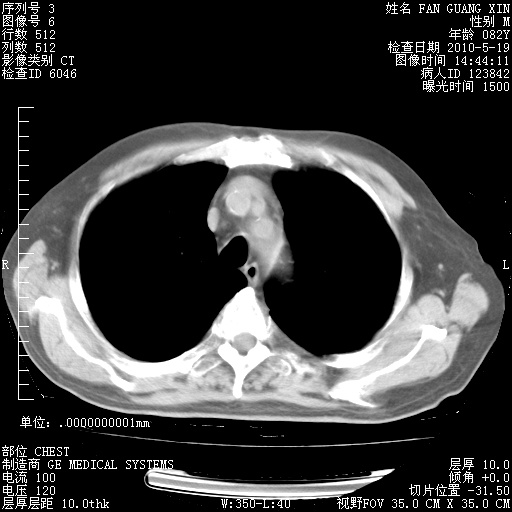

可改为口服强的松40-50mg/d治疗,若病情仍稳定,胸部阴影不再吸收可逐渐减量